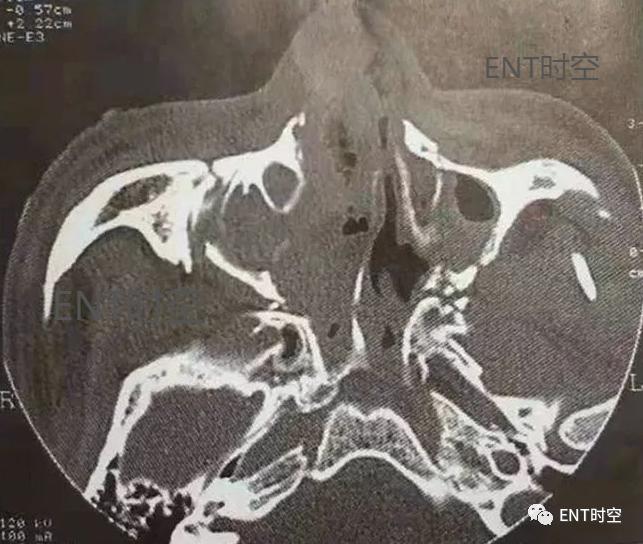

3、筛窦骨折:筛窦位于筛骨蜂房结构中,骨壁菲薄,筛骨纸板构成眶内壁,筛板构成前颅窝底,介于鼻腔顶和筛窦之间。单纯筛窦骨折少见,多为复合性骨折。(图1、2)

图1鼻-鼻窦多发骨折。轴位CT显示鼻骨、右侧上颌骨额突、鼻中隔及眶外侧壁骨折。

图2鼻-鼻窦多发骨折,轴位CT示上颌窦各壁及翼突多发骨折,上颌窦内积血。